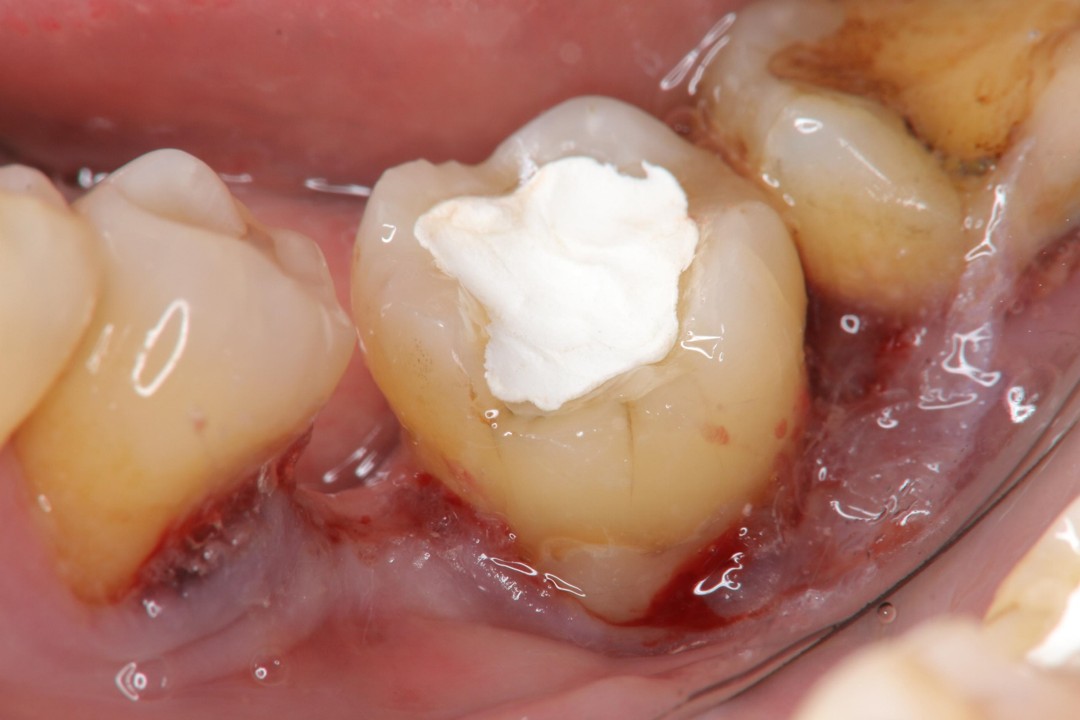

治療前,再次蛀牙,牙齒排列不整

蛀牙已至牙髓

水雷射牙冠增長手術及樹脂復形